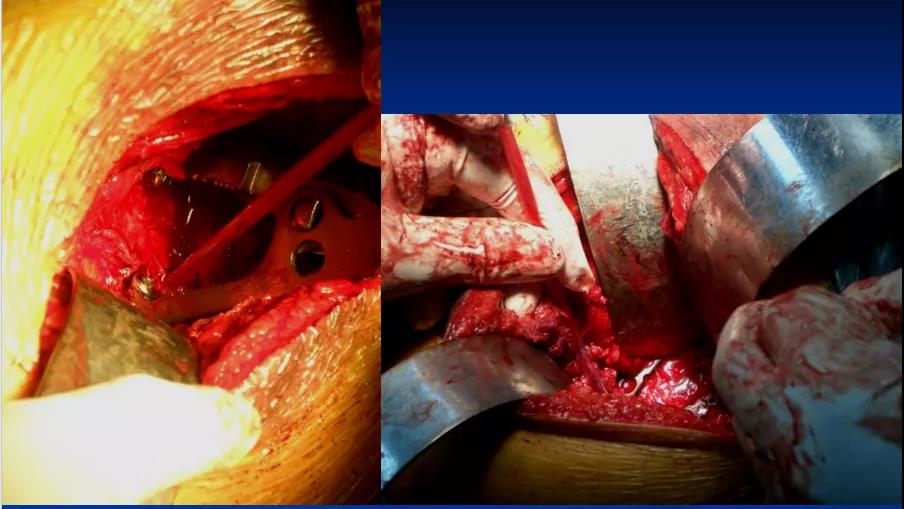

后方K—L入路联合前方髂腹股沟微创入路治疗复杂髋臼骨折:

2、一般先选择骨折移位大、粉碎较严重的后柱后壁骨折一侧 3、常先采取Kocher-Langenbeck后入路切口,改半俯卧位;切口:髂后上棘外下4cm处→经大转子顶点→ 垂直向下约5cm, 显露后柱后壁骨折

4、 以骨撬分别放在髂棘、坐骨大切迹、坐骨小切迹,显露后柱后壁骨折

5、根据CT情况探查关节腔,清除关节内的碎骨片; 6、a:解剖复位髋臼后柱及后壁;b:以重建钢板固定 c:纱布填塞切口 d:行C型臂透视了解前壁或前柱骨折复位情况;

7、后柱后壁解剖复位后,由于关节囊完整,前柱一般都能自然复位,对于后柱复位后,前柱骨折移位仍明显且复位该部位能明显修复整个髋臼的解剖序列和减少术后并发症的枢纽部位作为前入路的切开部位。前入路微创切口沿髂耻嵴插板,行前柱重建钢板内固定;

8、若采取前路髂腹股沟入路,改半仰卧位;切口:髂嵴和耻骨联合上;2 cm 两部位取切口;腹股沟区域不予切开显露

9、根据需要分别暴露前壁及前柱骨折部位:术中注意避免损伤髂腰肌及股神经束、髂外血管、精索或圆韧带死亡冠动脉

10、沿髂耻嵴插板,在耻骨上支用2枚螺钉固定,维持前柱,前壁解剖序列连续性,再髂骨上固定另一枚螺钉,起到断端加压作用。

——典型案例——

微创插板病历后路有限切开,结合前路微创插板内